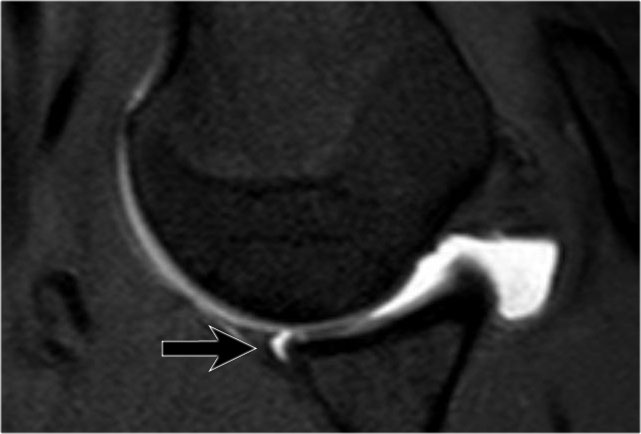

Đây là một bệnh nhân khác có Bankart xương được thấy trên bốn hình ảnh liên tiếp của MRI khớp cản từ ở tư thế ABER.

Lưu ý đường viền bất thường của ổ chảo phía trước và bờ trước bị avulsion (mũi tên)